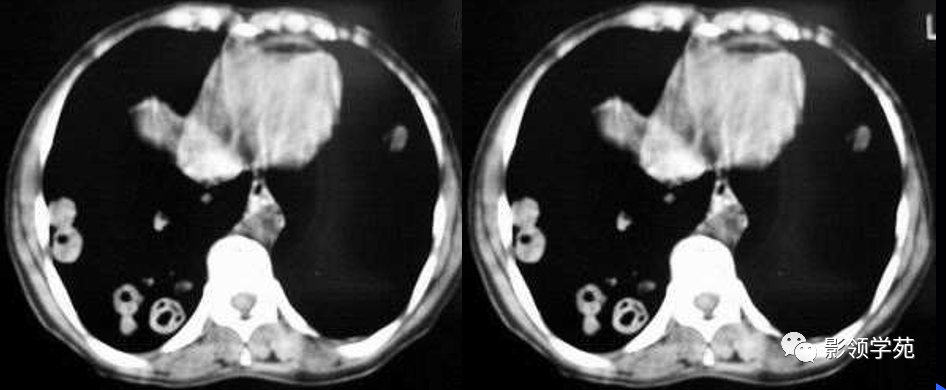

肺转移瘤。

肺窗像(A)示双肺野可见大小不等的圆形高密度结节影,纵隔增宽;纵隔窗像(B)示肺内肿块呈实性,纵隔满布大小不等的肿大淋巴结

CT诊断:甲状腺癌双肺多发转移